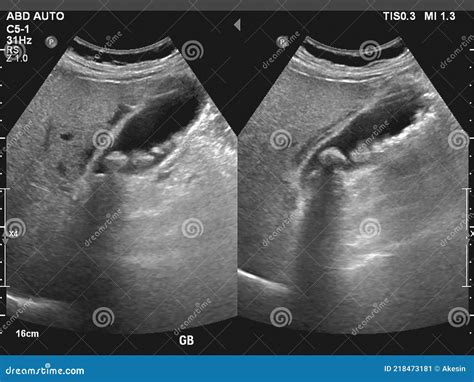

Understanding the internal health of your digestive system often begins with curiosity about what might be causing abdominal discomfort. Many patients who experience sharp pain in their upper right abdomen start their research by looking for Gallbladder Stones Pictures to visualize what might be occurring inside their bodies. Gallstones, or cholelithiasis, are hardened deposits of digestive fluid that can form in your gallbladder—a small, pear-shaped organ on the right side of your abdomen, just beneath your liver. While seeing medical imagery can be unsettling, it is an essential part of understanding the physical reality of a condition that affects millions of people worldwide.

Gallstones vary significantly in size and appearance, ranging from as small as a grain of sand to as large as a golf ball. When searching for Gallbladder Stones Pictures, you will likely notice that they are rarely uniform. They are typically composed of either cholesterol or bilirubin, a pigment found in bile. The formation process usually involves an imbalance in the chemical makeup of bile stored in the gallbladder. If the bile contains too much cholesterol or too much bilirubin, these substances begin to crystallize and harden over time.

When medical professionals perform an ultrasound or a CT scan, they use specific imaging techniques to locate these deposits. In Gallbladder Stones Pictures taken from clinical settings, stones are categorized into three main types based on their composition:

Modern medicine relies heavily on sophisticated scans to see what is happening in the biliary tract. Unlike generic Gallbladder Stones Pictures found online, medical-grade imaging provides a precise map of the gallbladder, the bile ducts, and the presence of any blockages. An ultrasound remains the most common first-line test because it is non-invasive and does not use radiation.